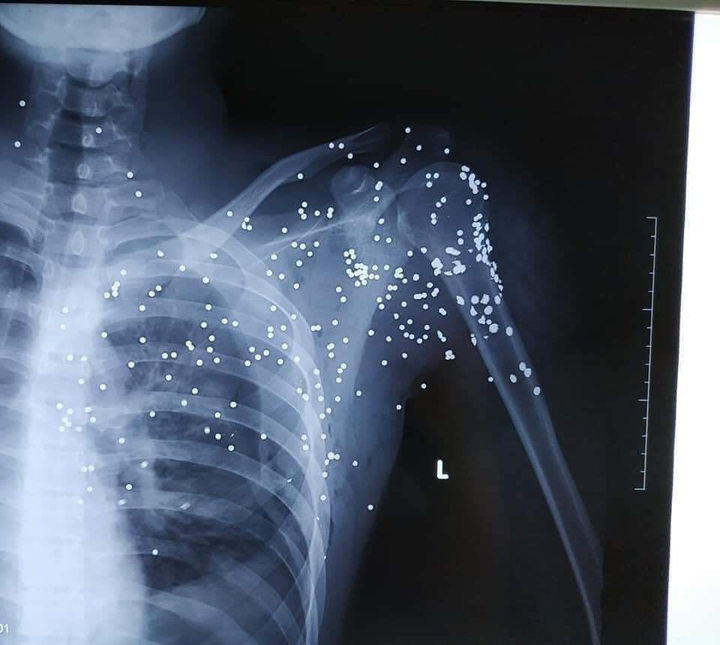

Những vết đạn chi chít trên cơ thể nạn nhân.

Như VTC News đưa tin, khoảng 20h ngày 23/11, anh B.H.H (19 tuổi, trú tại xã Bình Minh, huyện Kiến Xương) từ xe ô tô xuống quán nước gần Trạm thu phí Thanh Nê (nằm trên đường 39B thuộc địa phận xã Bình Minh) thì bị Bùi Xuân Đại mở cửa xe khách, dùng súng hoa cải bắn.

Sau đó, kẻ này rời đi. Anh H. được gia đình và người dân đưa đi cấp cứu tại Bệnh viện Đa khoa tỉnh Thái Bình trong tình trạng đa chấn thương, mất nhiều máu.

Sau khi được sơ cứu, các bác sĩ chuyển bệnh nhân lên Bệnh viện Hữu nghị Việt Đức (Hà Nội) tiếp tục điều trị.